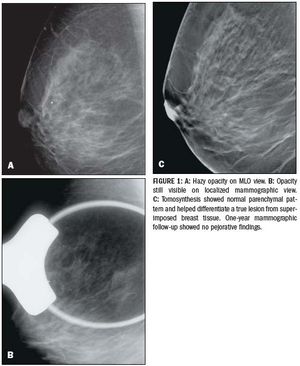

Breast tomosynthesis tackles new challenges

ByCaroline Malhaire, MD,Fabienne Thibault, MD

Mammography is the only screening modality that has been proven to reduce mortality from breast cancer.